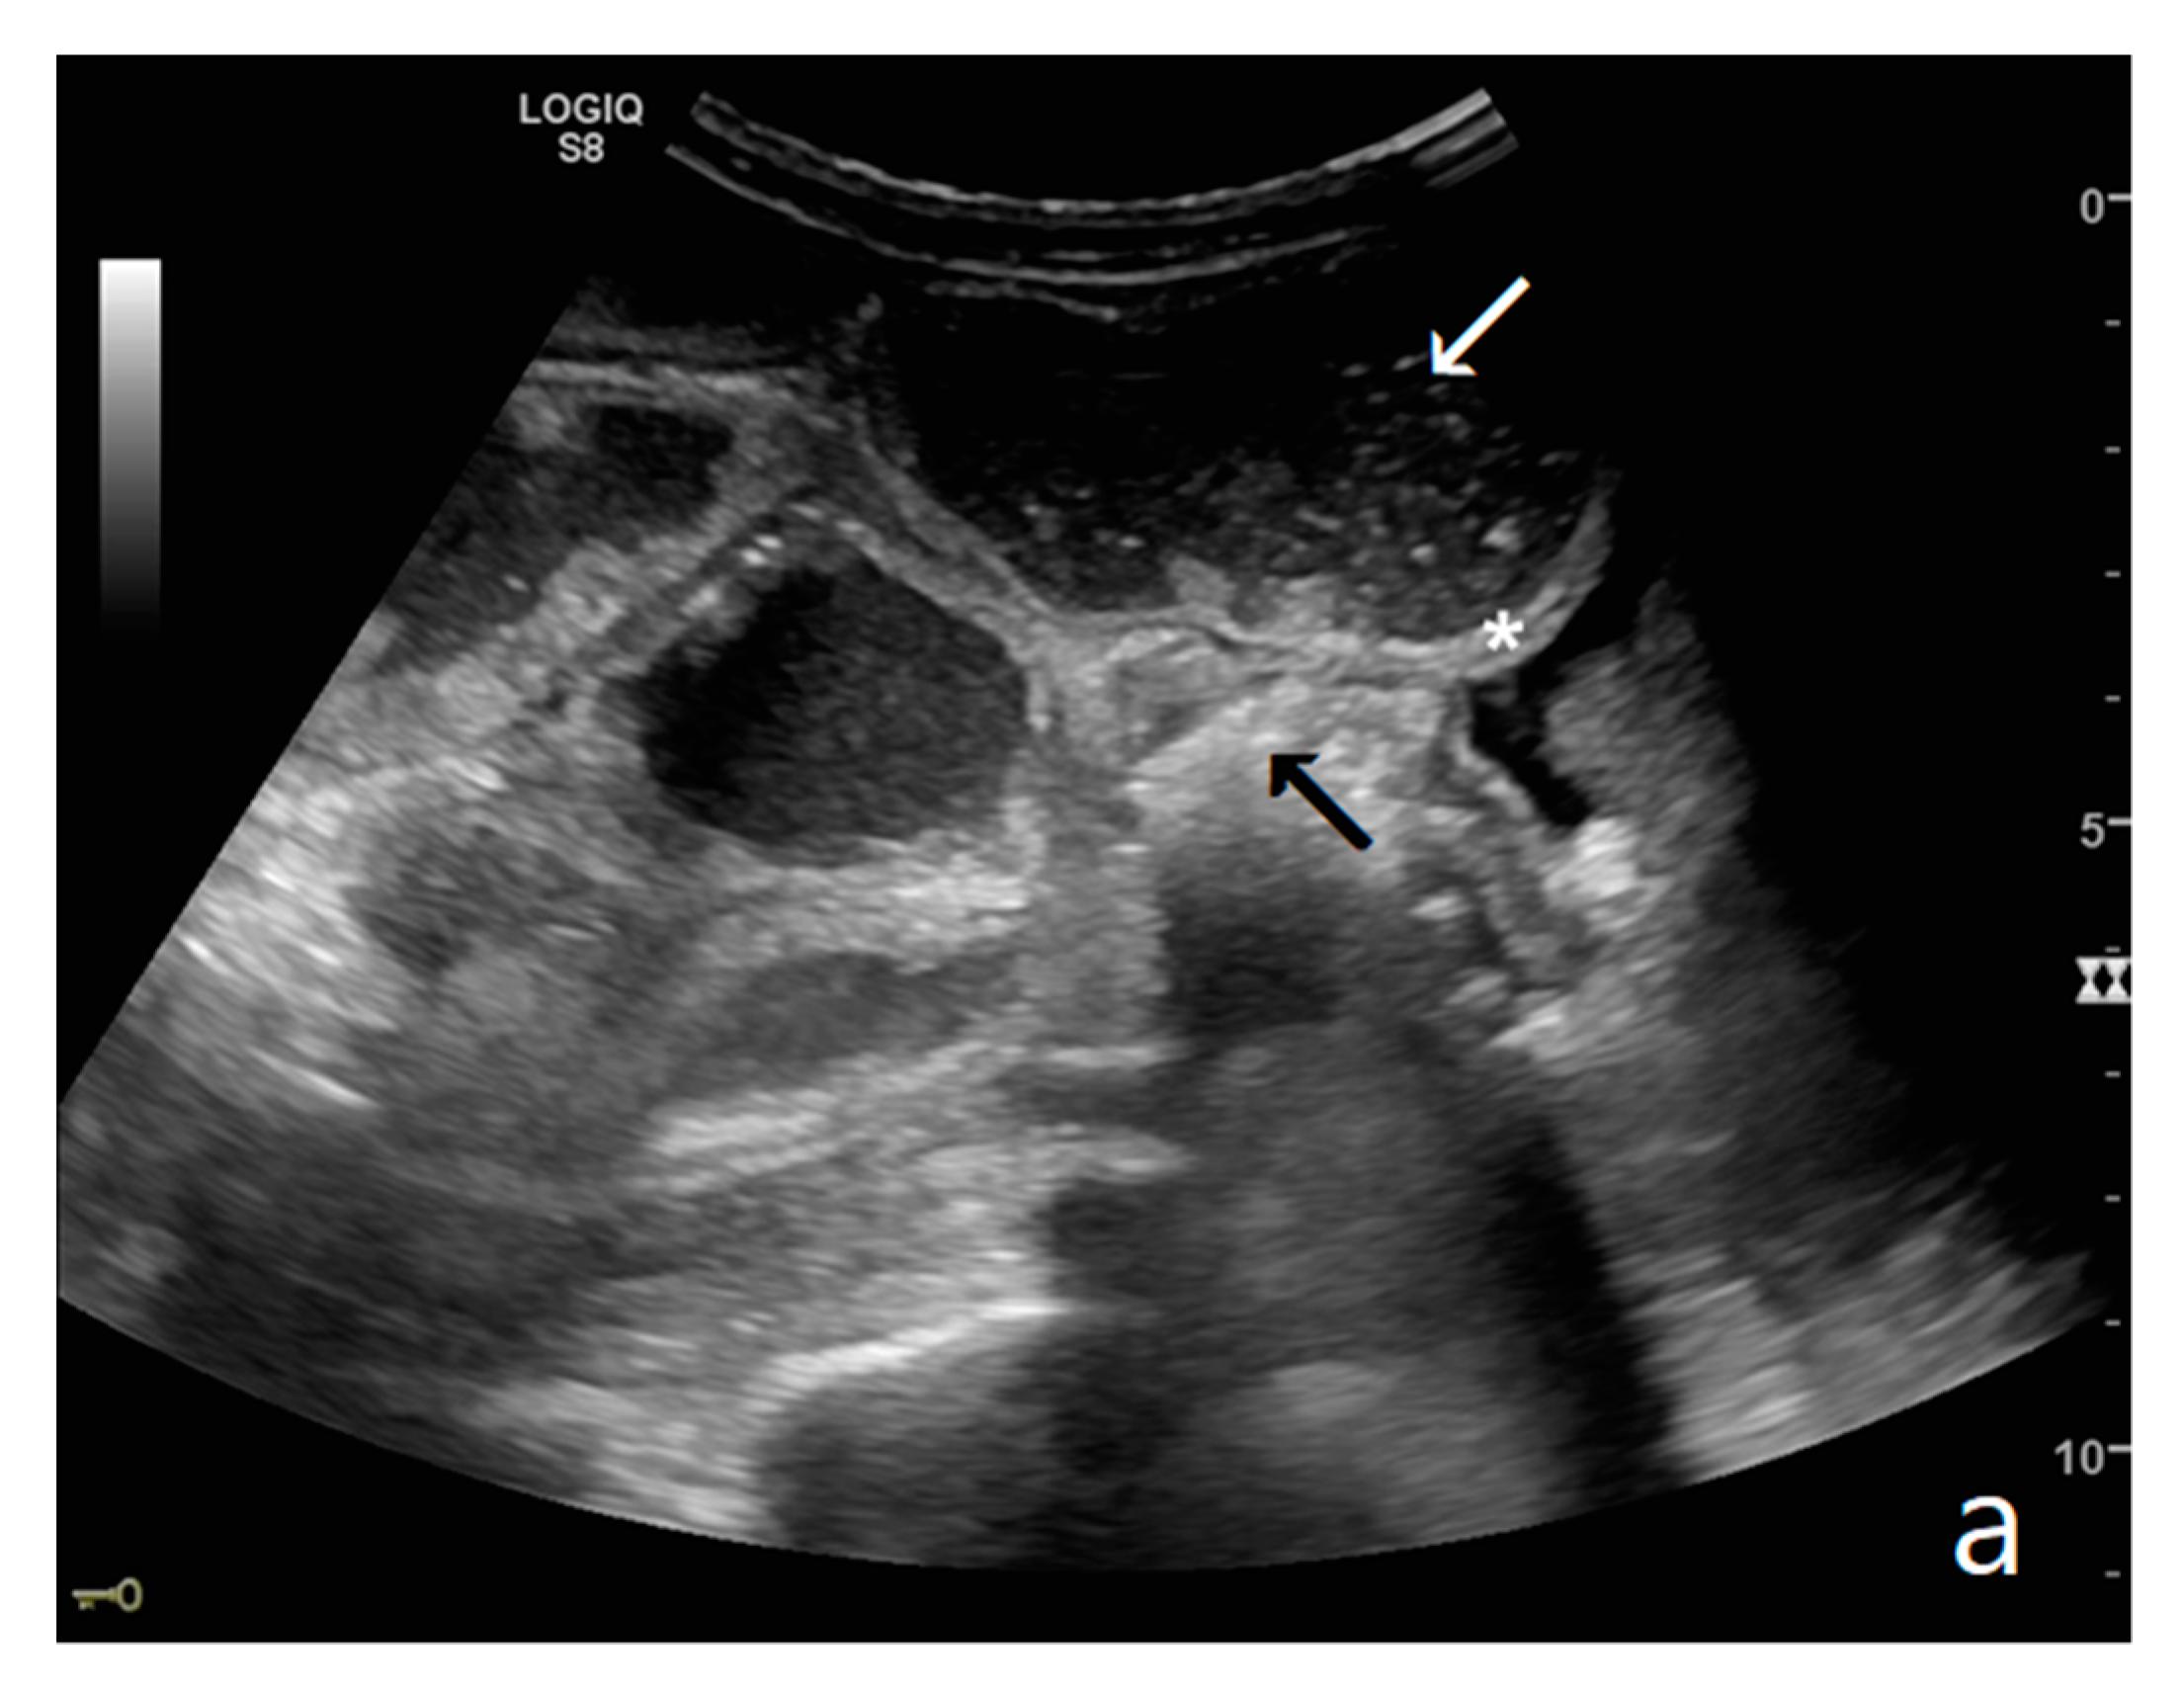

Figure 2.

A dilated small bowel loop with a caliber of more than 3 cm (dotted line) with trapped feces defines a ‘small bowel feces sign’. Bowel walls appear thin, and the folds flatten.